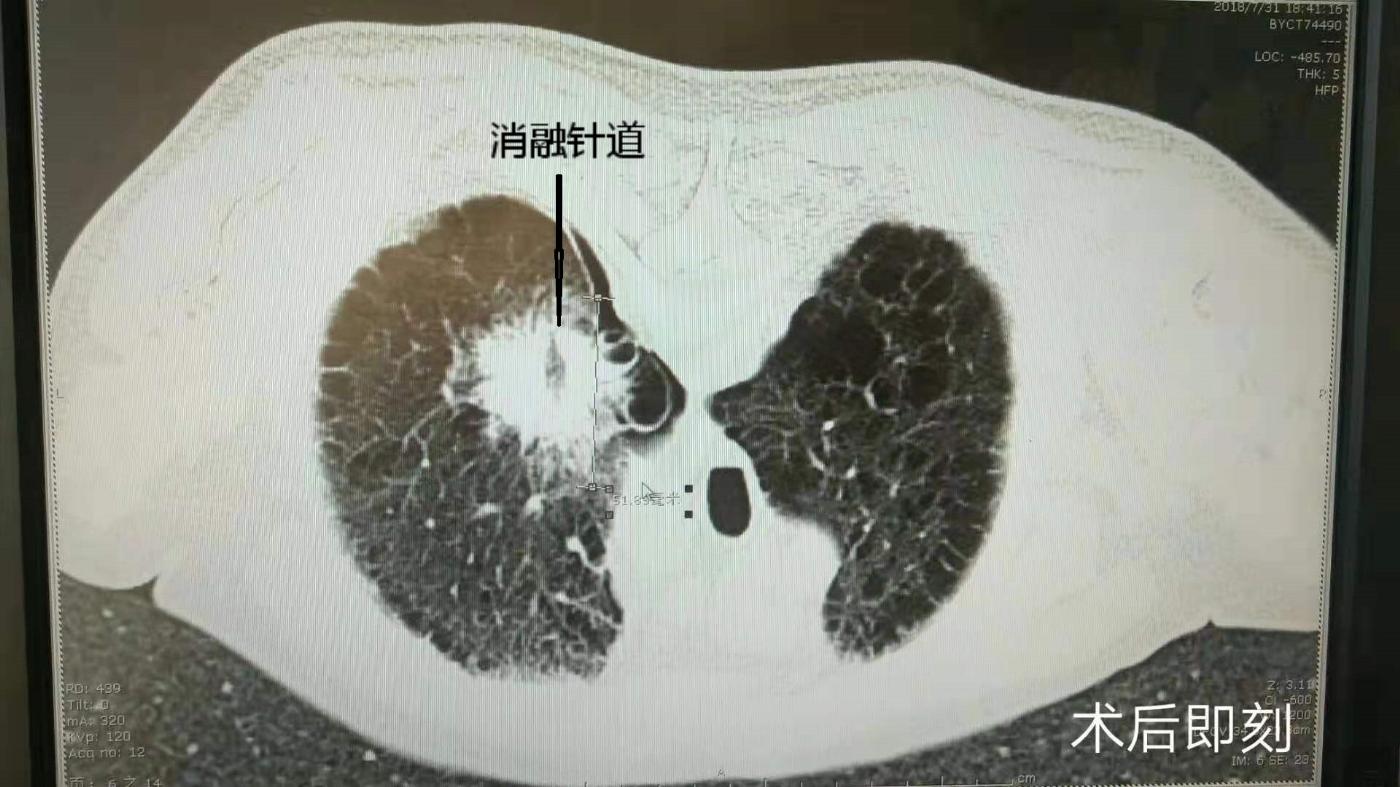

目前肺癌已经成为居于第一位的肿瘤杀手,肺脏因为血液及淋巴循环丰富,肺部转移瘤的发现也越来越多,肿瘤的治疗大多数首选外科手术切除,但由于各部位肿瘤在数量、大小、部位、合并症以及发病年龄等方面的多样性和复杂性,外科切除单一的方法越来越难以满足患者的需求。CT引导下热消融治疗原发性和转移性肺部肿瘤是目前国内发展迅速的一门新技术,该技术微创、精准、安全,并且能够保全脏器功能。CT引导下微波消融可实时监测靶区范围变化,并可以根据CT扫描结果决定下一步方案。